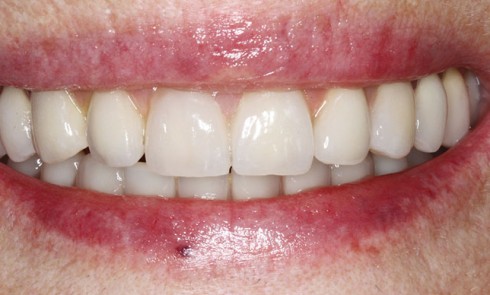

Article réservé à nos abonnés Protocole de mise en charge en 36 heures chez l’édenté total

De nos jours il est presque inconcevable de proposer un traitement implantaire au patient en voie d’édentement au maxillaire sans...